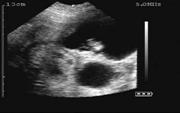

26 days of gestation

28 days of gestation

30 days of gestation